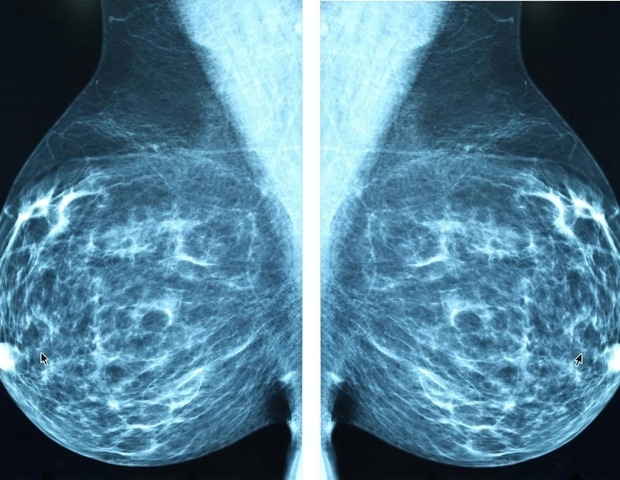

Though a common procedure, mastectomy, which involves the removal of one or both breasts, is a major surgery that requires long-term follow-up care. More than a quarter of patients with breast cancer typically undergo a mastectomy, and many patients are staying in the hospital for shorter periods after surgery*- a trend that prompted the investigators to analyze patients’ outcomes after mastectomy through a systematic review.

Out of nearly 3,000 studies they identified, researchers analyzed 20 studies that met their inclusion criteria, examining the effects of mastectomy on quality of life, sexual health, and psychosocial well-being. All the articles focused on the experience of women with Stages 1-3 breast cancer. Studies involving women with Stage 4 breast cancer, as well as women who elected for a prophylactic mastectomy for cancer risk reduction, were excluded from the study due to the distinct needs and different overall medical decision making for these patients.